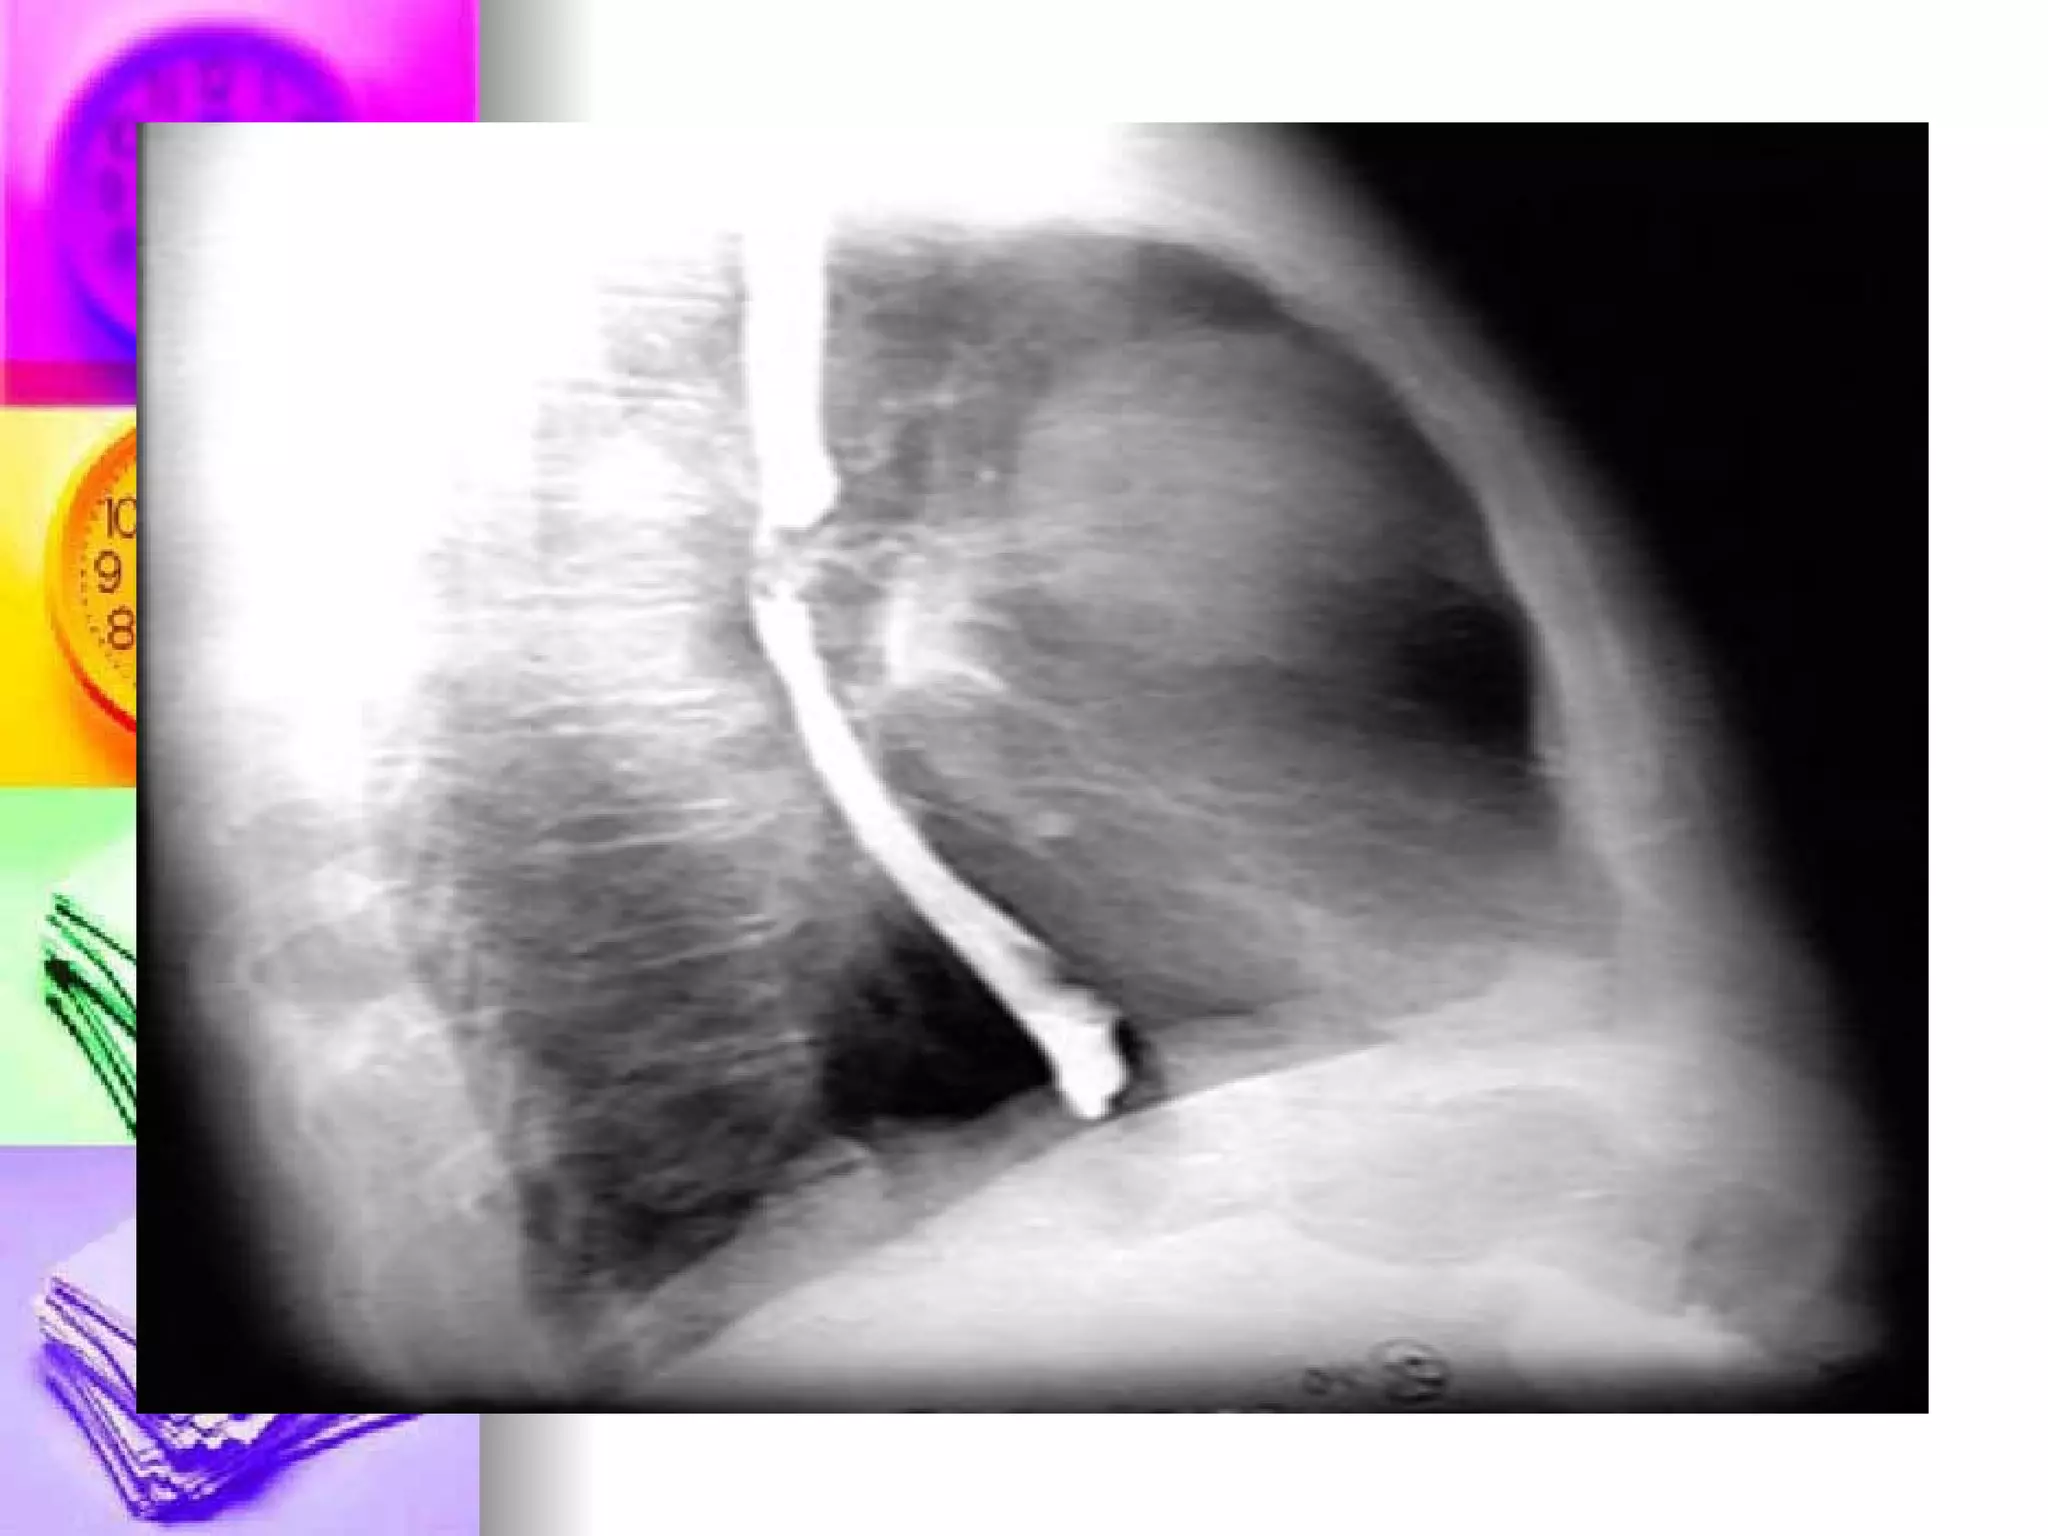

Bronchoscopy Purpose: Diagnostic and therapeutic Pretest:  Consent, NPO, client teaching, anti-anxiety drugs Intratest : gag reflex is abolished, instruct to remain still during procedure, FOWLER or  SUPINE Post-test : NPO until gag reflex returns, monitor patient for complication like perforation/bleed

Bronchoscopy Purpose: Diagnosticand therapeutic Pretest: Consent, NPO, client teaching, anti-anxiety drugs Intratest : gag reflex is abolished, instruct to remain still during procedure, FOWLER or SUPINE Post-test : NPO until gag reflex returns, monitor patient for complication like perforation/bleed